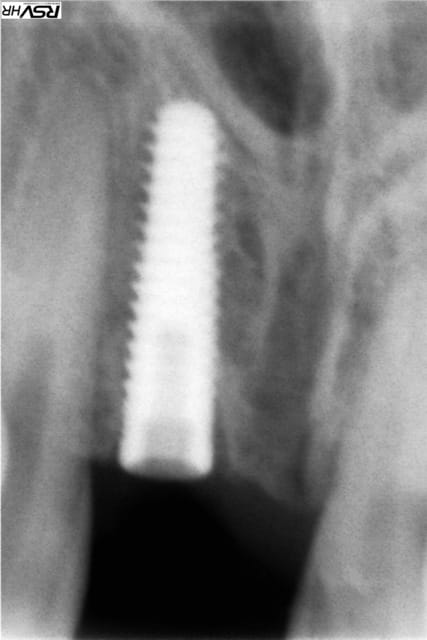

> Implant Legacy (ayé) 3 4,2x16mm

juste une toute petite remarque: je l'aurais un poil plus enfoui cet implant 1/3 de tour (0.6mm) histoire d'anticiper la résorption osseuse post extractionnelle...et de bénéficier pleinement du concept de plateform switching que t'offre le legacy3 en 4.2mm...mais bon...et comme les copains, tu t'es un peu trop laissé diriger par ton alvéole...mais çà le fera quand même...

regarde les photos...le pilier prov pour le legacy3 en 4.2mm DOIT être un pilier 3.5!!!!

pourquoi? le 3.5 a un cône (à 44°) le 4.5 (pour implant 4.7 et 5.2) a une plateforme plate suivie d'un cône lui aussi à 44°...

bien sûr l'hex est identique (2.5mm) MAIS en utilisant ce pilier:

- tu ne portes que sur une "arrête" de plastique et non sur tout le cône...

- ton hex en plastique ne descend pas à fond dans l'hex de l'implant!!!!!!!!!!

bilan: tu n'as pas d'étanchéité, très peu de stabilité et c'est la vis qui encaisse tout!!!!!

refais très vite ta prov en utilisant le bon pilier, sinon prie pour pas qu'il y ait de casse!!!!